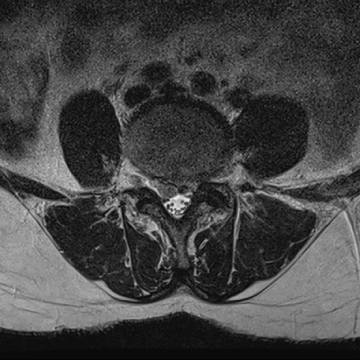

허리 디스크 수술 전·후

2022.08.01

2022.08.04

ㆍ환자 동의를 받은 자료이며, 이미지 사진은 실물과 다를 수 있습니다.

ㆍ모든 자료는 새움병원 자료입니다.